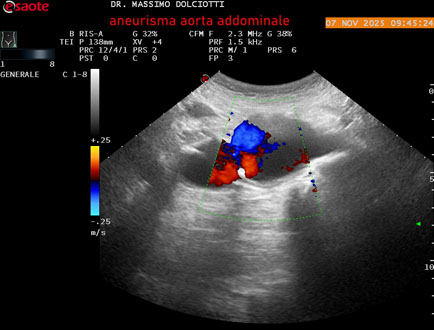

Data inserimento: 11/11/2025

Ecografia del: 07/11/2025

Strumento: Esaote MyLab Eight

Sonda: Convex Multifrequenza 1-8 MHz

Età Paziente: M 60 anni

Motivazione dell'esame: follow up per aneurisma dell'aorta addominale.

Commento all'esame: le immagini ed il video documentano la presenza dell'aneurisma dell'aorta addominale sotto-renale, con diametro antero-posteriore massimo documentato di 47 / 48 mm.

Conclusioni: aneurisma dell'aorta addominale in follow up (abdominal aortic aneurysm follow-up).

Presentazione: Dr. Massimo Dolciotti - Ancona

Elaborazione digitale: Andrea Dini - Ancona